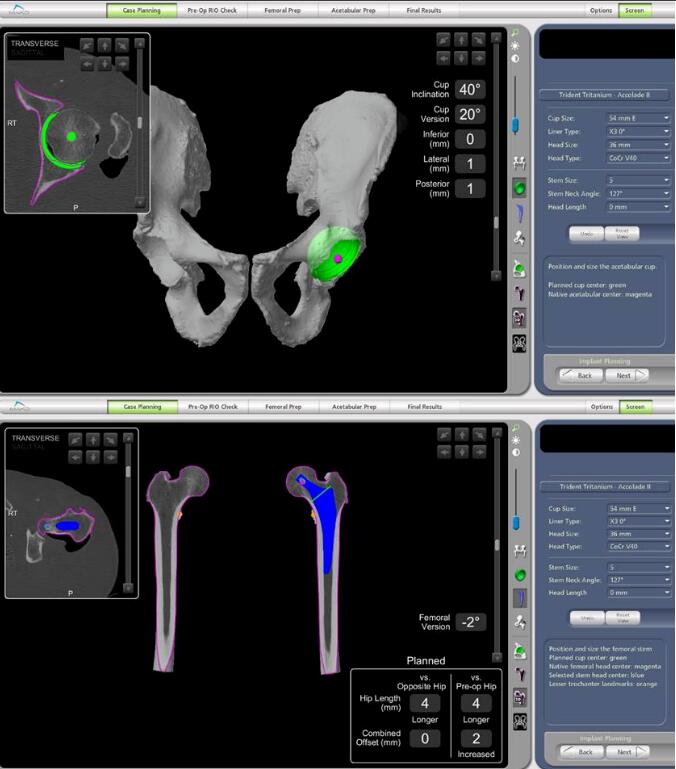

Mako智能机器人是一款基于智能手术规划技术和智能辅助截骨技术的关节手术机器人,系统囊括了临床诊断、术式设计、手术虚拟仿真、疗效评价、手术导航和远程医疗等。

机械臂、导航模块和摄像立架是Mako机器人的核心组成部分,它们犹如人的“手臂”、“大脑”和“眼睛”,将传统的手动手术过程转化为数字化规划,通过“术前完整的手术规划”、“术中1度和1毫米的精准截骨与假体植入”,实现人工关节的高精度植入,使其完美适配人体关节的生理结构与活动需求,达成“精准微创、加速康复”的治疗目标。

利用患者术前CT数据构建3D骨骼模型,通过导航模块在专属3D模型图像上规划植入物尺寸与摆放位置,对安装效果和截骨量、截骨角度等进行提前“预演”,实现精准术前方案定制。

2、术中:实时动态平衡与智能防错

手术中系统实时捕捉软组织张力,关节面的接触点,髋关节的前倾角,下肢长度,旋转中心,偏心距等临床信息,医生据此调整手术计划,实现关节平衡并达到1度1毫米个性化放置。当操作偏离预设路径0.1毫米,机械臂触发阻力反馈、警报并终止操作。

借助限制性立体定位边界与三维可视化截骨界面,独有的反馈式机器臂辅助医生实现精准截骨与假体精准安放。患者不仅恢复更快、使用体验更佳,同时有效降低磨损率与并发症,延长假体使用寿命,让“一次置换用终生”成为可能!